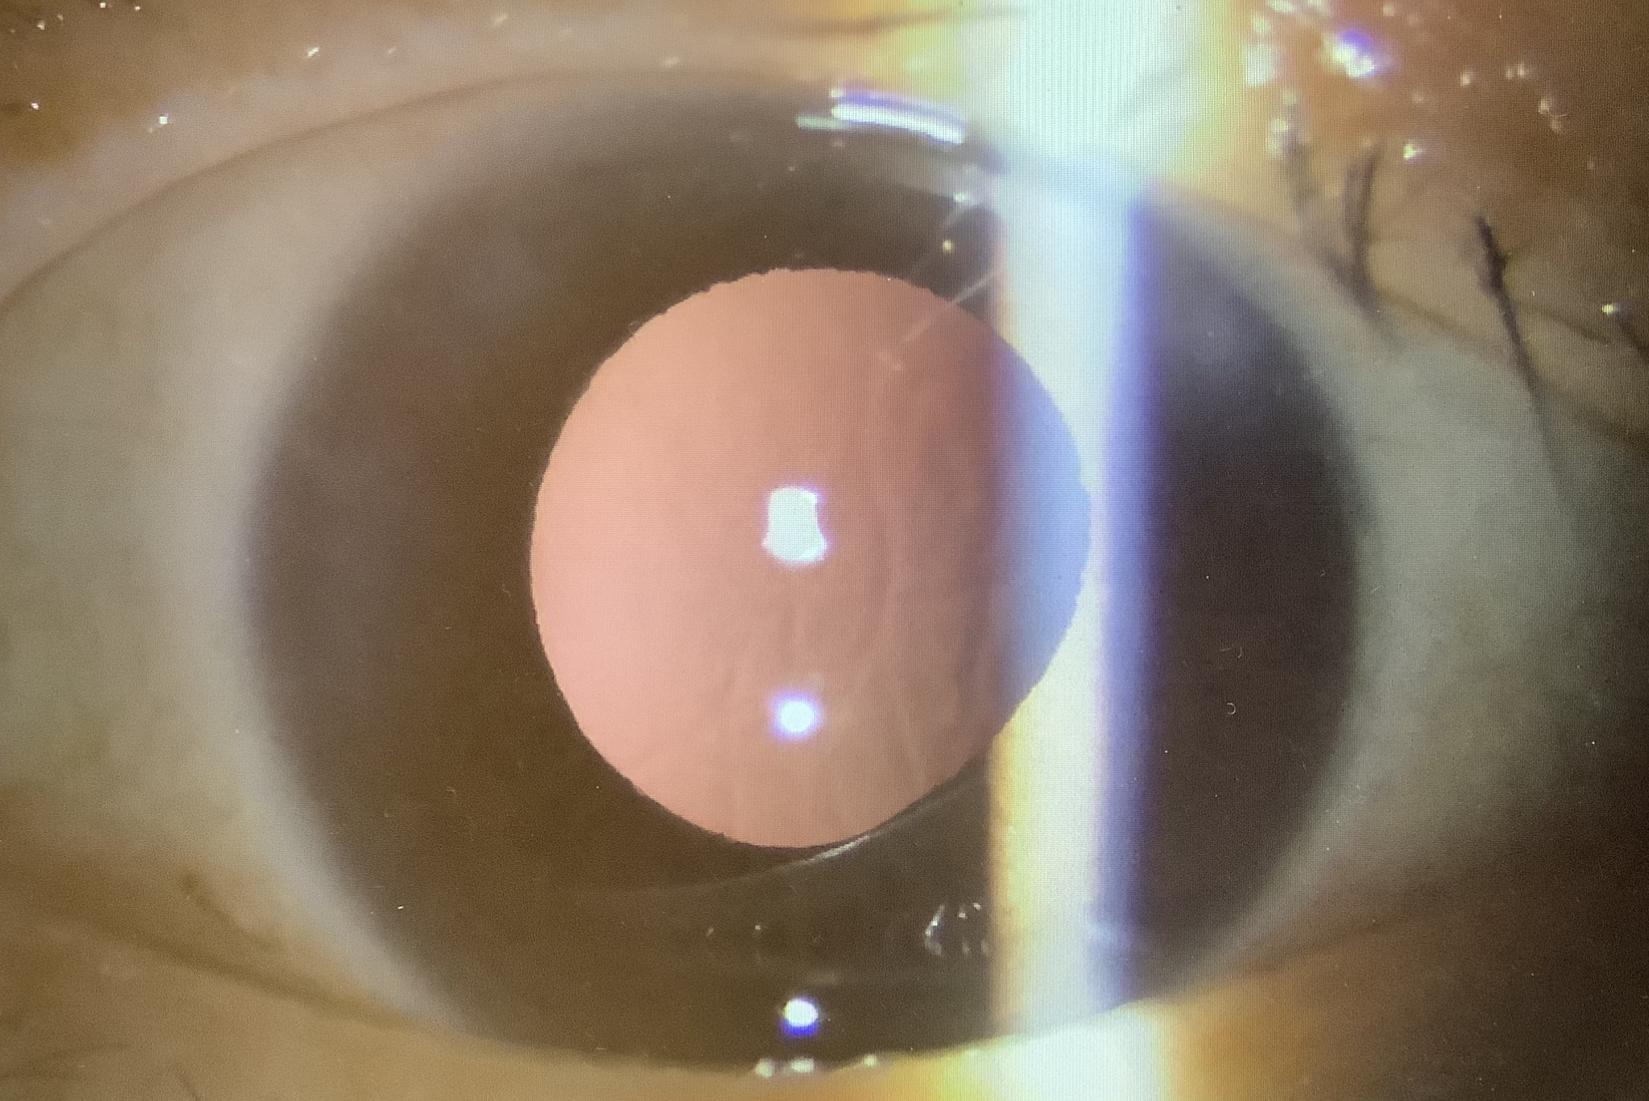

昨日の白内障手術の60代の女性の方は、当院に来る前に受診した眼科では、『手術不可』と言われていたそうですが、確かに白内障の濁りが表面は真っ白で中はまっ茶色の“過熟白内障”で、尚且つ、水晶体の支え(チン小帯)が弱い、ちょっと大変な白内障でした。白内障が真っ白になっていると、水晶体の表面を切開するCCCという操作がしにくいのですが、なんとか無事CCCを完成させましたが、水晶体の内部の濁りがかなり硬く、超音波で破砕吸引するうちに、元々弱いチン小帯に負荷がかかり、眼の壁から水晶体嚢が外れてしまう“チン小帯断裂”が起こり、なんとか水晶体の濁りは取り除いたものの、水晶体嚢は残すことができませんでした。このようなケースでは、眼内レンズを眼の中に入れるために、レンズの支えの部分を眼の壁に埋め込む“強膜内固定”という方法を行っています。本当は一度の手術でレンズを入れるところまで行いのですが、当院では強膜内固定用のレンズはその都度、発注する必要があることと、手術時間が1時間くらいかかってしまい、その後の患者さまを皆さんかなりお待たせしてしまうことになってしまうため、レンズの入らなかった患者さまには申し訳ないのですが、強膜内固定は後日改めて行わせていただいております。

水晶体や眼内レンズのない“無水晶体眼(アファキア)”の状態では、ピントが合わないので、裸眼ではかなり見えにくく不便をしてしまいますが、きちんとレンズを入れれば、見えるようになりますので、心配せずにお待ちいただければと思います。ちなみに、この患者さまは術前は手動弁でほとんど見えませんでしたが、濁りが取れたので、アファキアでも0.03と少し見えるようになっていました。来週の水曜日に強膜内固定を予定させていただいたので、もう少しお待ちください。